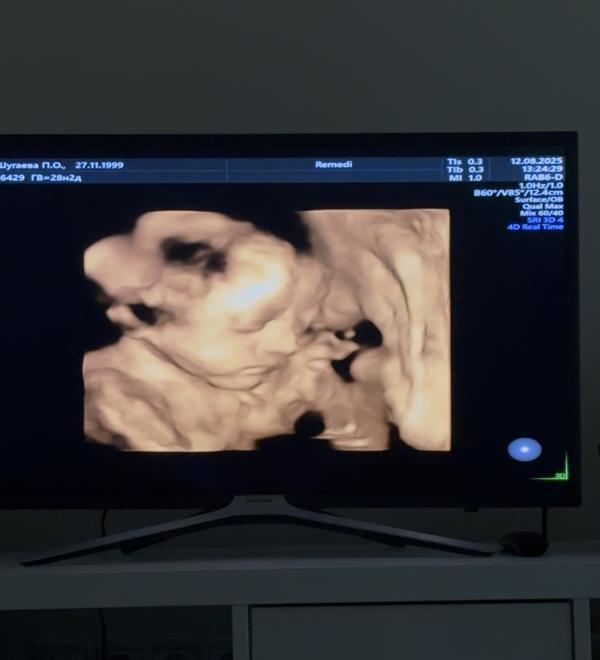

Сверху сегодняшнее узи доченьки в животе и снизу старшая дочка

Как считаете похожи?😁

Да, очень 💗